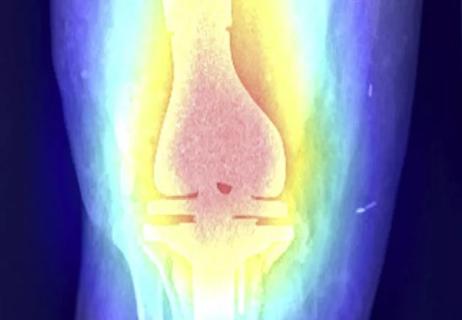

Although platelet-rich plasma (PRP) is becoming more common in the treatment of osteoarthritis, soft tissue injuries, tendinopathies and muscle tears, it needs more development and optimization, says Nicolas S. Piuzzi, MD, Director of Cleveland Clinic Adult Reconstruction Research.